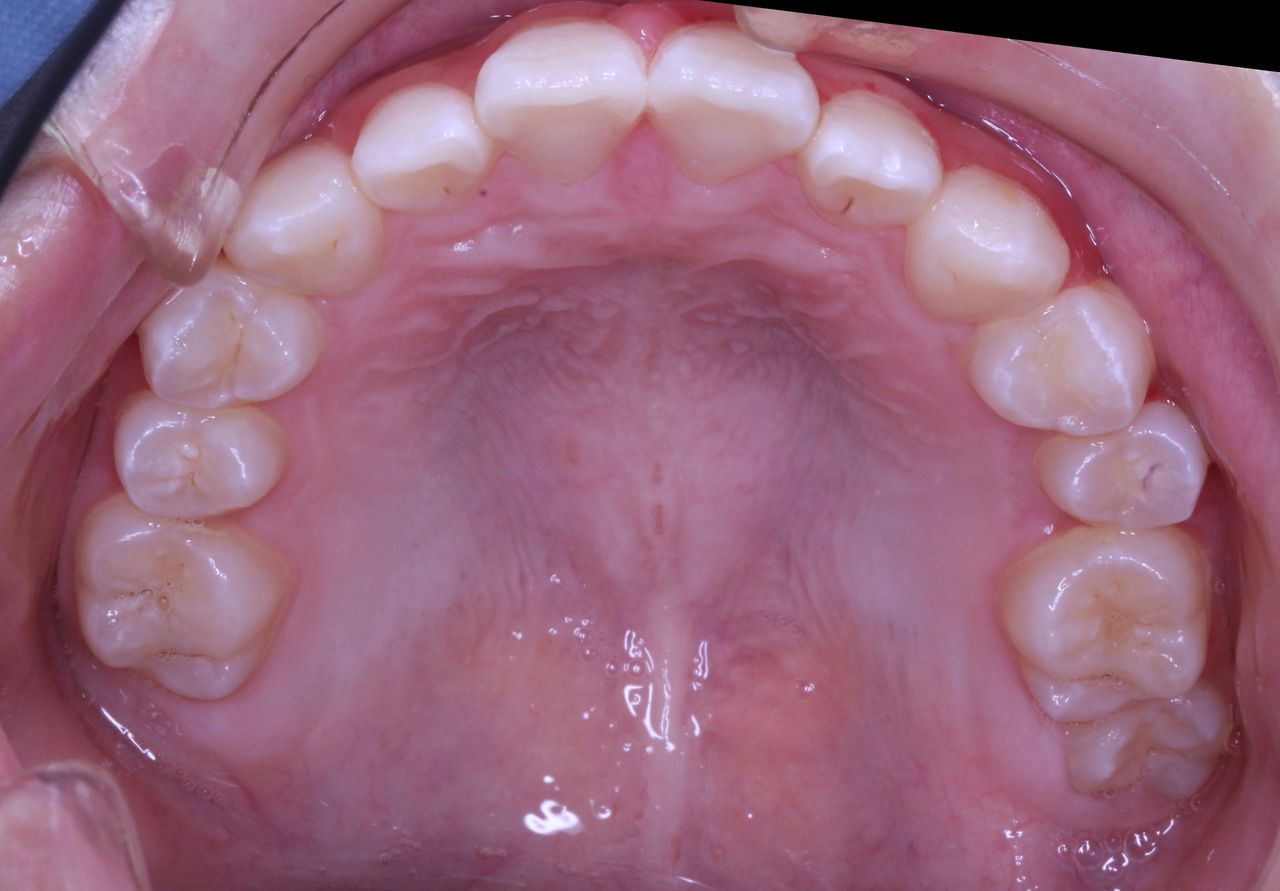

経過をみていくと、変な部分から大人の歯が生えてきました。

乳歯列時期に重篤な虫歯になった場合、あとから生えてくる永久歯は変な場所から生えてくることが多々あります。

理由は、乳歯が虫歯菌によって感染している状況下において、その上にある永久歯の卵はそのままの状況では自分も感染してしまいます。 まれに感染してしまった大人の歯は色が黒ずんだり、形がいびつな奇形的な歯になってしまいます。 多くの場合は感染した乳歯から離れていくのです。 つまり、永久歯の卵は避難しているわけです。

この状況をふりかえってみてもそうでした。

変なところから生えてきた永久歯を正常な方向に誘導するためには、その隣の乳歯も抜歯せざるを得ない状況になってしまいました。

また、一方でそうなると、反対側の乳歯の交換も促進していかなければ左右対称な歯列が完成しません。

この状況ではいくつかの乳歯をいっぺんに抜歯するといった処置をおこなう必要がありました。